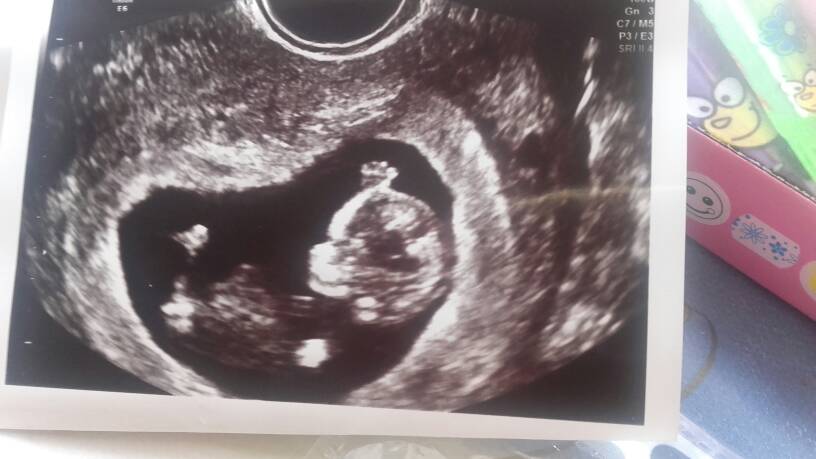

Dawno mnie tu nie bylo. Ale jakoś wygodniej na Facebooku jest pisać. Troche sie rozchorowałam ale juz jest troszkę lepiej. Na ostatniej wizycie było dobrze ale musiałam zakupić ciśnieniomierz bo coś mi skacze. I musze juz teraz zrobić krzywą cukrową. Maluszek ma juz 9 cm i skacze jak szalony z rękoma do góry. [emoji1]